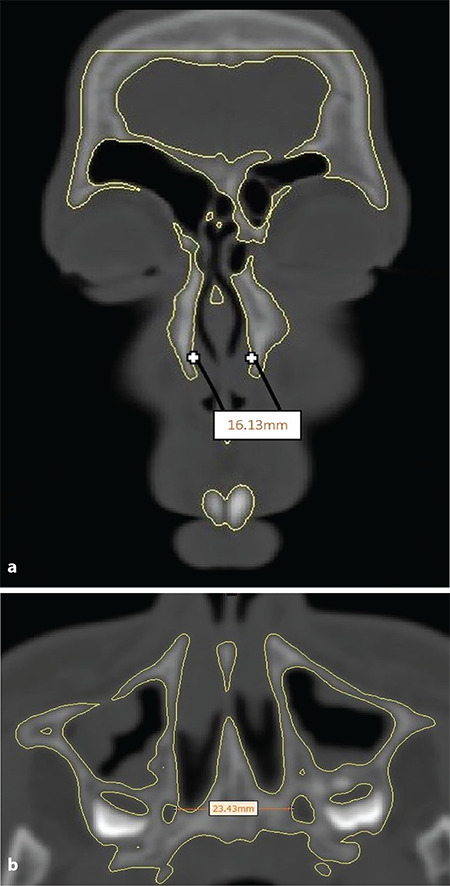

Methods: A Digital Imaging and Communication in Medicine dataset of 20 patients (mean age: 15.55 years) prior (T0) and after (T1: 3.5±0.5 months) to RME were retrieved from the archive and analyzed. Bone density values of midpalatal suture (MPS), zygomaticomaxillary suture (ZMS), zygomaticotemporal suture (ZTS), pterygopalatine suture (PPS), and transverse palatine suture (TPS) were measured. The cervical vertebral maturational stages (CVS) were examined. The linear distances between the most lateral points of the piriform apertures were measured as the anterior reference, and the medial margins of the greater palatine foramina on the axial slice were chosen as the posterior reference. The difference at T1-T0 was calculated as the skeletal response to RME at anterior and posterior skeletal references. Spearman's rho rank and Kruskal-Wallis tests were used.

Results: Mean density values of ZMS, PPS, ZTS, TPS, MPS-Anterior, and MPS-Posterior were 922.81, 807.44, 753.83, 640.77, 661.13, and 604.59 HU, respectively. Mean linear changes in anterior and posterior skeletal expansion were 2.93±1.78 and 1.93±2.52 mm. There was no significant relationship between maturation indicators and skeletal response. Significant relationships were found between CVS and MPS density and CVS and circummaxillary suture average density (p≤0.05).